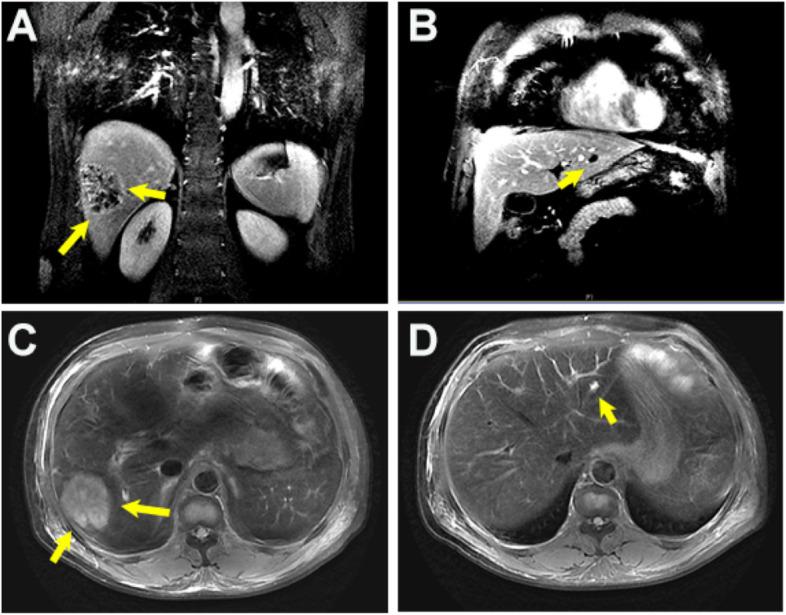

A 54-year-old male patient came to our department with a fever for 2 days and altered mental status for 1 day. Abdominal computed tomography (CT) and liver magnetic resonance imaging (MRI) revealed multiple liver abscesses. The blood culture was identified as Klebsiella pneumoniae sepsis. Head contrast-enhanced MRI and magnetic resonance venography (MRV) imaging showed multiple thrombus formation in the right transverse sinus and sigmoid sinus. The patient's infection and thrombosis were controlled within one week of multidisciplinary comprehensive treatment such as antibiotic and antithrombotic therapy, and a good clinical recovery during the 1-month follow-up.

一名 54 岁男性患者因发热 2 天伴精神状态改变 1 天来我院就诊。腹部 CT 和肝脏 MRI 显示多发肝脓肿。血培养鉴定为肺炎克雷伯菌败血症。头部增强 MRI 和磁共振静脉造影(MRV)成像显示右侧横窦和乙状窦多发血栓形成。经过多学科综合治疗(如抗生素和抗血栓治疗)一周后,患者的感染和血栓得到控制,在 1 个月的随访期间临床恢复良好。